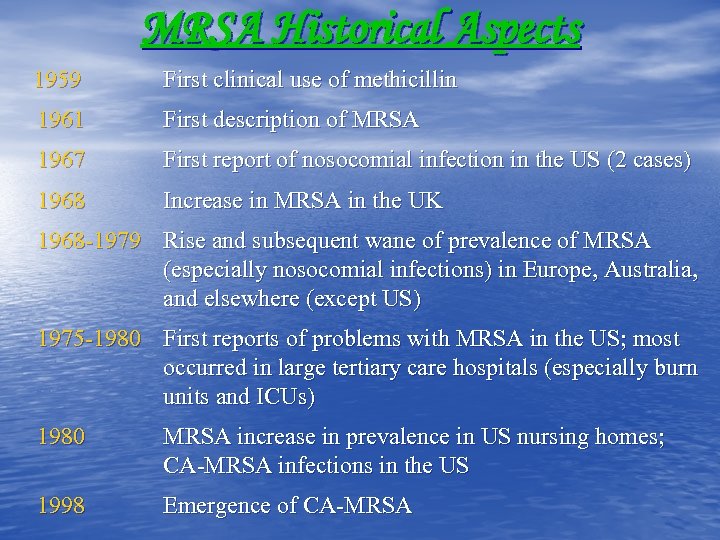

MRSA Historical Aspects 1959 First clinical use of methicillin 1961 First description of MRSA 1967 First report of nosocomial infection in the US (2 cases) 1968 Increase in MRSA in the UK 1968 -1979 Rise and subsequent wane of prevalence of MRSA (especially nosocomial infections) in Europe, Australia, and elsewhere (except US) 1975 -1980 First reports of problems with MRSA in the US; most occurred in large tertiary care hospitals (especially burn units and ICUs) 1980 MRSA increase in prevalence in US nursing homes; CA-MRSA infections in the US 1998 Emergence of CA-MRSA

MRSA Historical Aspects 1959 First clinical use of methicillin 1961 First description of MRSA 1967 First report of nosocomial infection in the US (2 cases) 1968 Increase in MRSA in the UK 1968 -1979 Rise and subsequent wane of prevalence of MRSA (especially nosocomial infections) in Europe, Australia, and elsewhere (except US) 1975 -1980 First reports of problems with MRSA in the US; most occurred in large tertiary care hospitals (especially burn units and ICUs) 1980 MRSA increase in prevalence in US nursing homes; CA-MRSA infections in the US 1998 Emergence of CA-MRSA